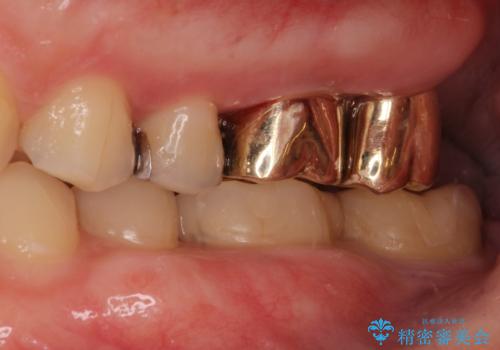

- 銀歯をやりかえたいが他院で抜歯と言われセカンドオピニオンで来院。適合の悪い被せ物が入っており、まずは古い材料、虫歯をとり保存可能か確かめる必要があり、拡大鏡下で全て取り除いたら歯質が歯茎の中まで虫歯がありました。このまま無理やり型取りをして被せ物を作っても不適合な被せ物が入る可能性が高いため歯茎を切り取る手術(ディスタルウェッジ)を行いました。そして再根管治療を行いゴールドの被せ物で治療を行いました。

- PGAクラウン・仮歯 13.2万円×2 精密根管治療(リトリートメント)・コア 16.5万円×2 ディスタルウェッジ 1万円費用は治療当時の料金となります

適合の良い被せ物が入り大変満足して頂けました。